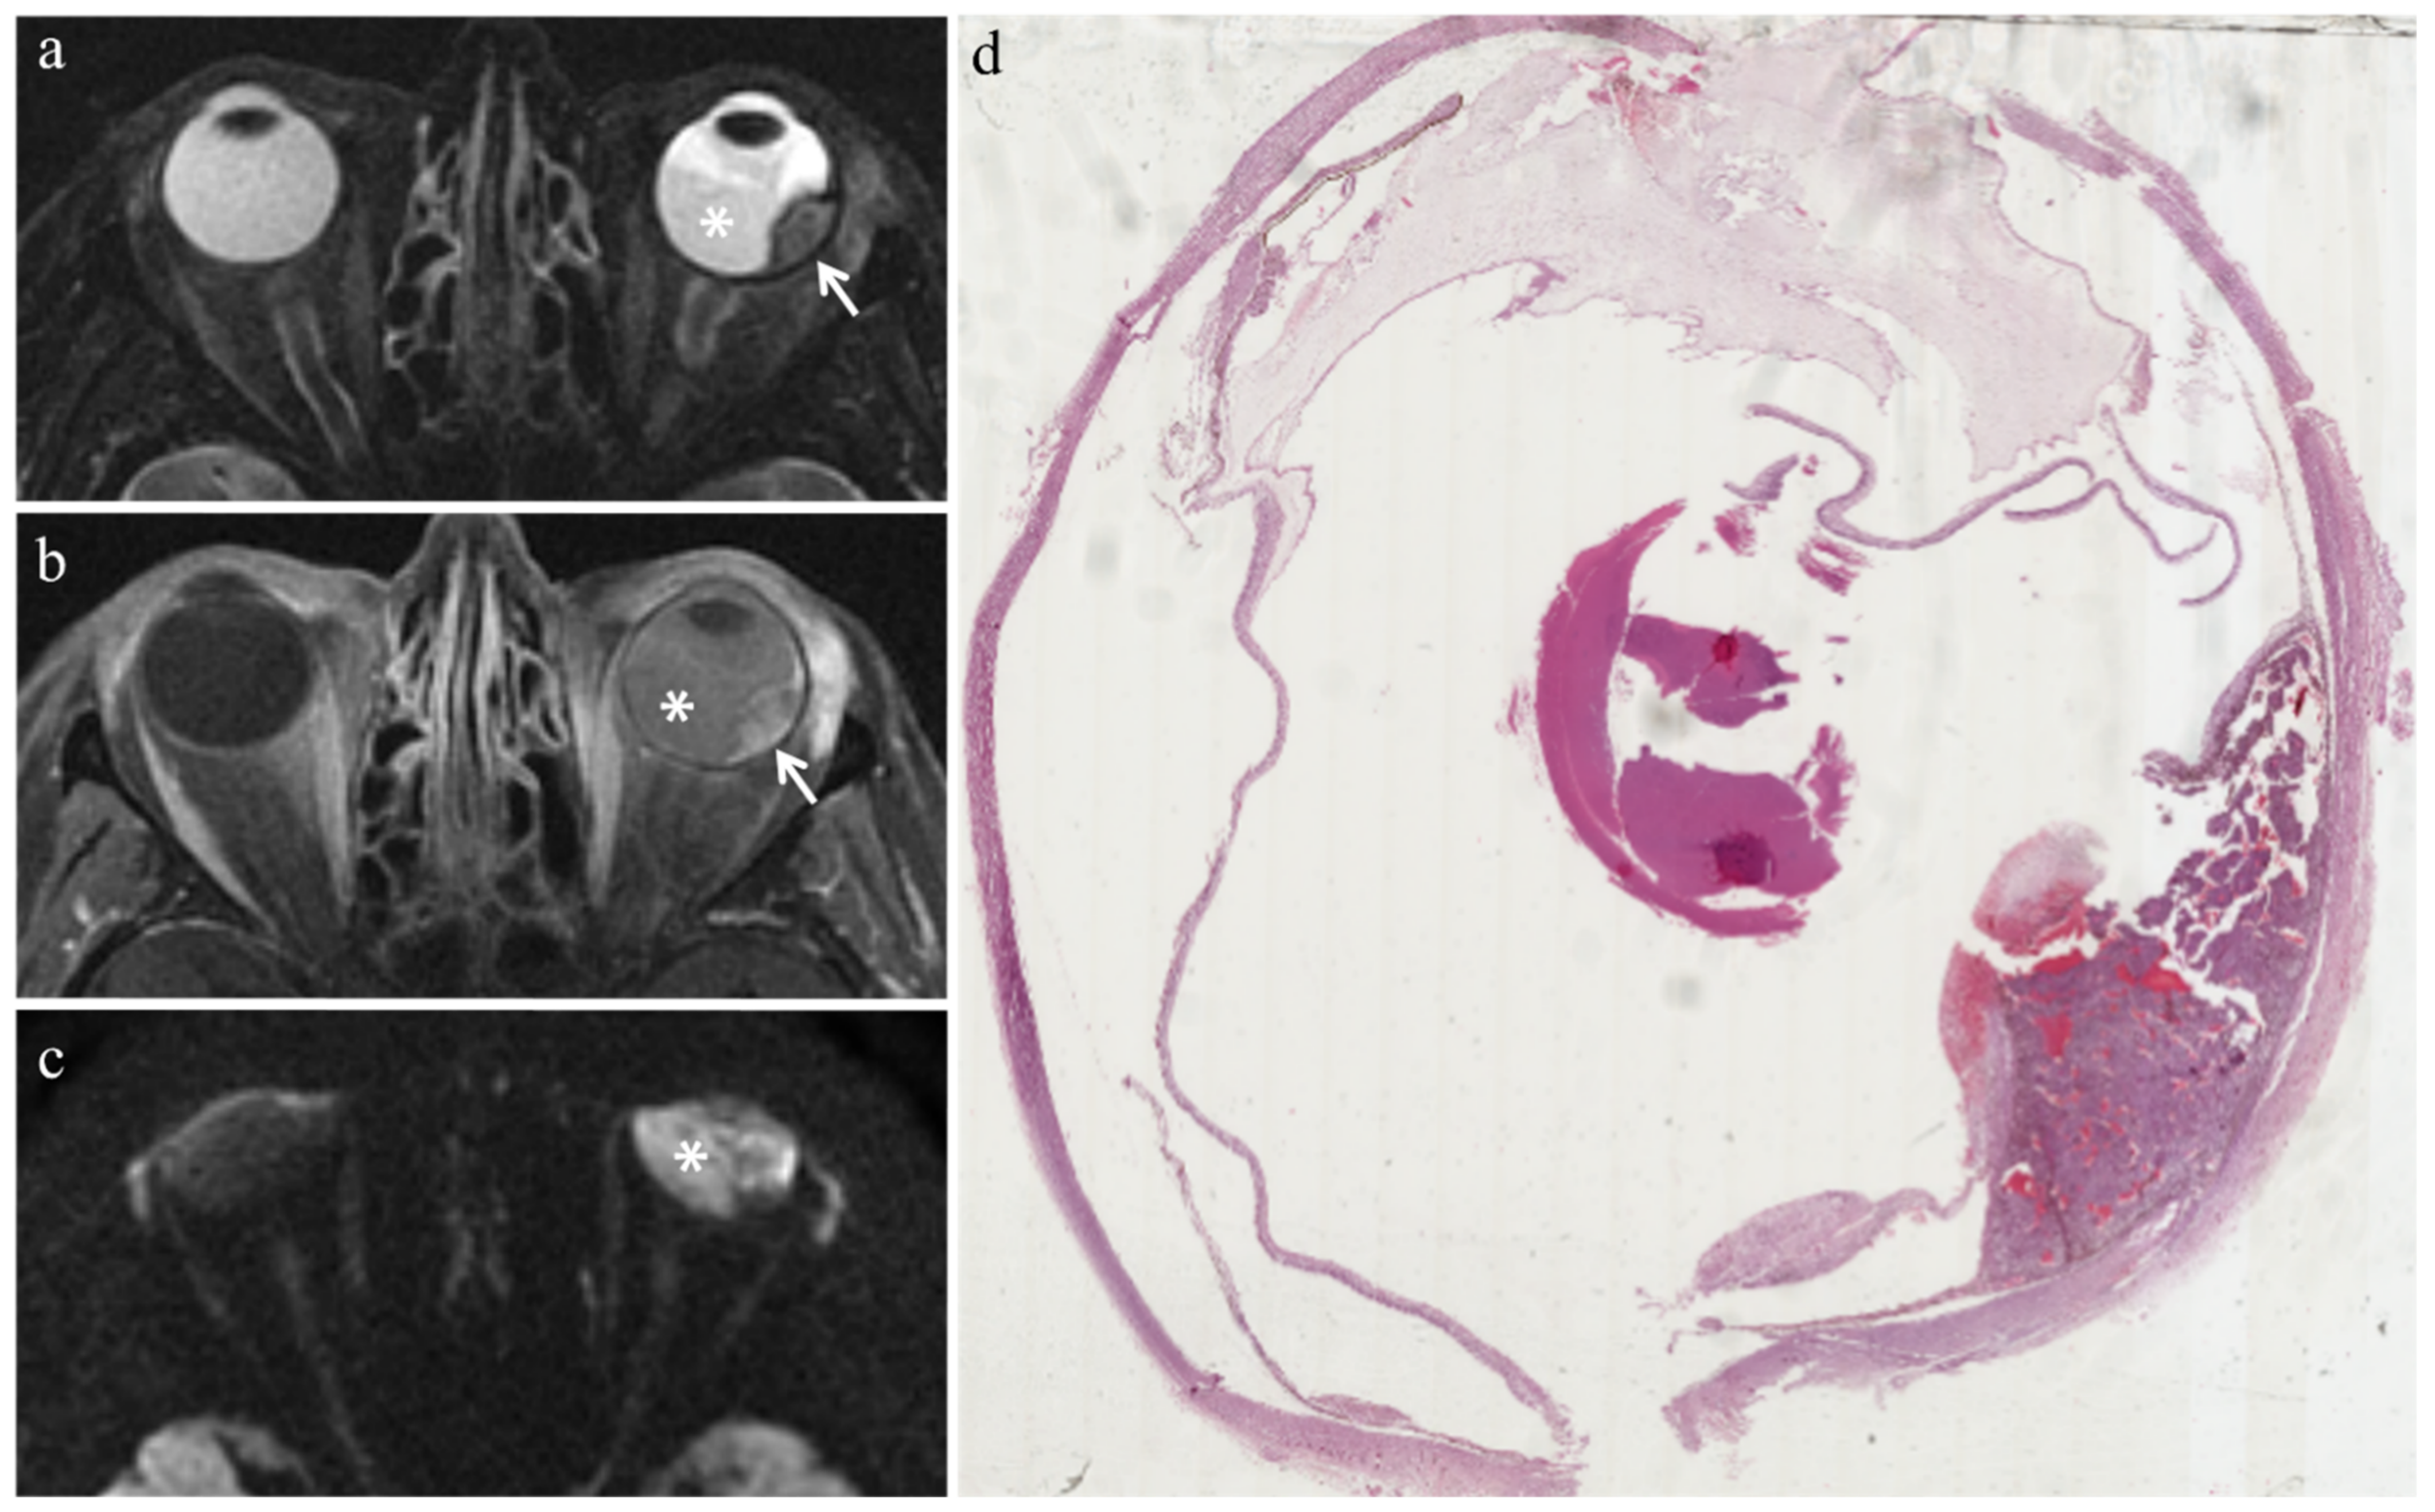

| Patient | Histologic Type | Radiation-Induced Necrosis Histology MRI | Fibrosis Histology MRI | Viable Tumor Tissue Histology MRI | |||

|---|---|---|---|---|---|---|---|

| 2 | Necrosis without viable tumor tissue | Yes | Yes | - | - | - | - |

| 3 | Spindle cell | Yes | Yes | - | - | Yes | Yes |

| 4 | Epithelioid cell | Yes | Yes | - | - | Yes | Yes |

| 7 | Spindle cell | Yes | Yes | - | - | Yes | Yes |

| MR Finding | T2 | T1 | Gd-T1 | DWI |

|---|---|---|---|---|

| Radiation-induced necrosis | ![]() Low signal | ![]() High signal | ![]() No enhancement | ![]() Low signal |

| Fibrosis | ![]() Low signal | ![]() Intermediate signal | ![]() Moderate enhancement | ![]() Low signal |

| Viable tumor tissue, pigmented melanoma | ![]() Low signal | ![]() High signal | ![]() Enhancement of viable tissue | ![]() High signal |

| Viable tumor tissue, poorly pigmented melanoma | ![]() Intermediate signal | ![]() Intermediate signal | ![]() Enhancement of viable tissue | ![]() High signal |

low signal;

intermediate signal;

high signal;

no enhancement;

enhancement of the viable tissue.| MR Finding | T2 | T1 | Gd-T1 | DWI |